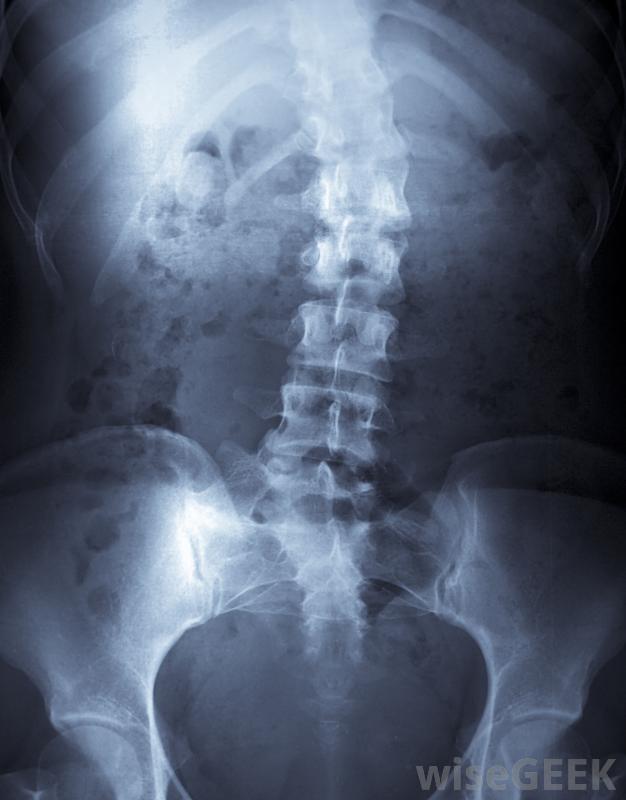

TLSO支架是一種主要用于脊柱側凸兒童的脊柱支架。該支架安裝在軀干上方并支撐背部。除了在脊柱側凸治療中的作用外,TLSO支架也可用于背部受傷或背部手術后恢復的成人和兒童。 一些兒童可能需要佩戴支架以防止脊柱側凸...

是胸腰椎骶骨矯形器的縮寫。TLSO支具也可稱為Boston支具或腋下支具。它們通常由耐用塑料制成,并專門成型以適合兒童身體。

胸腰椎骶骨矯形器支架通過對脊柱各點施加壓力來對抗脊柱側凸。隨著時間的推移脊柱讓位給背帶的壓力,背部的彎曲慢慢變直。這種類型的脊柱側凸矯正器戴在衣服下面,旁觀者幾乎看不見。戴TLSO支架的兒童通常一天能保持23小時,盡管它通常在劇烈的體力活動中被移除。